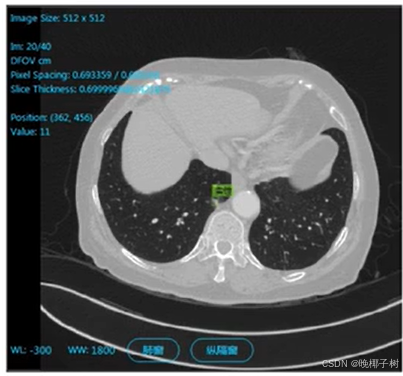

*图像分类中样本量过少的问题

· 样本量极少:样本获取较难导致总体样本量过少。

医疗